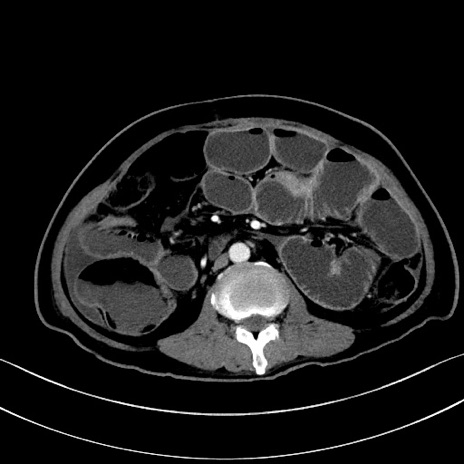

症例28(横断像)

【症例】60歳代男性

【主訴】嘔吐

【現病歴】胃癌にて胃全摘後。食思不振が悪化し、夜中に嘔吐することがある。

【既往歴】胃癌、胃全摘、脾摘、胆摘後

【データ】WBC 5900、CRP 10.56